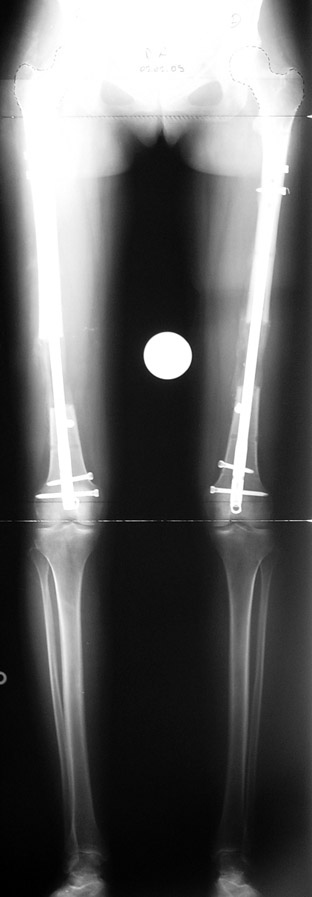

In selected cases, we prefer to use a combination of a unilateral dynamic axial fixator and an interlocked intramedullary nail, in order to protect the length and alignment after the completion of the lengthening procedure. As a prerequisite for this technique, the narowest diameter of the medullary cavity shall be wider than 7 mm and the length of the nail segment distal to the osteotomy site shall be at least 8 cm. after the completion of the lengthening procedure.The intramedullary nail neutralizes shear and bending forces on femur during lengthening, shortens external fixation time, and protects newly formed bone against fractures. In our series, subtrochanteric osteotomy was performed in one case. No varus angulation occured despite the intramedullary nail.

Ilizarov stressed the significance of endosteal blood circulation for distraction osteogenesis. Although we placed the intramedullary nail after reaming the femur in all cases, the time for callus formation was not longer than expected. Thus we found that there is no slowing in the rate of new bone formation due to disruption of medullary blood flow. The rationale of this finding is revascularization that occurs following reaming of the medullary cavity, the fixation stability with the intramedullary nail and early functional weight bearing. The potential disadvantages of a combined use of external and internal fixation metods are increased blood loss, intramedullary infection, risk of fat embolism and excessive metal load.The most fearsome complication is a deep intramedullary infection (panosteomyelitis) triggered by pin tract infection.No such complication was encountered in our series. In order to avoid this complication, after the completion of lengthening the nail shaill be interlocked from the medial side, and contact of internal and external fixator pins shall be avoided.

The combination of intramedullary anil and dynamic axial external fixator is harder as a technique than Standard Ilizarov applications. However, it is stil appealing due to the following advantages: shortening of the duration of external fixation, protection against refracture, early rehabilitation, gaining maximum range of motion and daily quality of life. These advantages are more important than disadvantages such as increased cost, increased blood loss and potetntial deep infection. All in all, we believe that the technique of femoral lengthening over an intramedullary nail is a safe and reliable method and provides advantages over standard Ilizarov aplications.